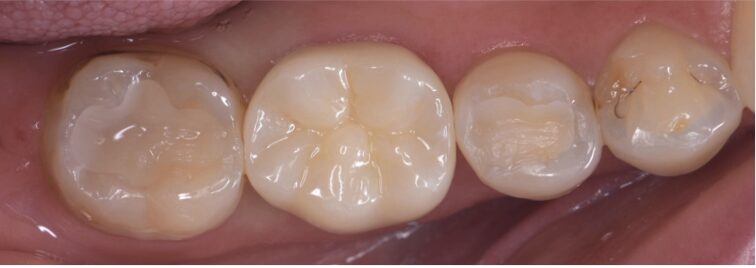

Before

右下の6番が痛みがあり噛めないが主訴でした。